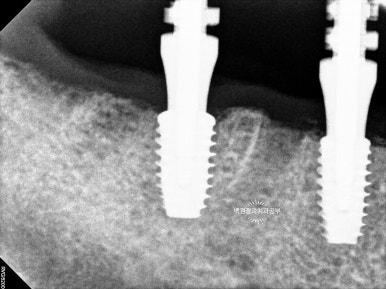

그리고 치과용 파노라마로 확인해보시면, 정확한 위치에 정확한 보철물이 제작되어 상당히 조화로운 결과를 확인하실 수 있으실거에요! 치과의사로 살면서 가장 기쁘고 감동적인 순간 중 하나입니다.